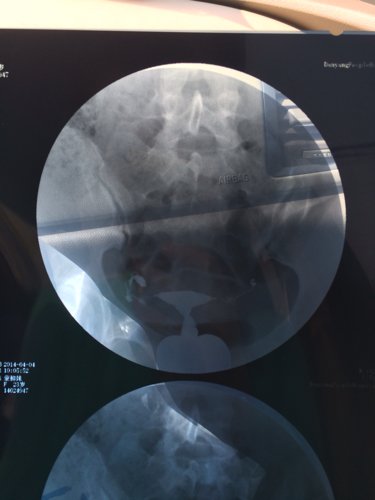

您好,医生。昨天我去做了一个子宫输卵管造影,结果检查所见子宫形态无明显异常。双侧输卵管伞部显影,双侧输卵管呈迂曲柔软的条状影。24小时后摄片示,造影剂在盆腔内积聚,弥散不良。检查结论双侧输卵管伞部碘油积聚,弥散不良,提示双侧输卵管伞部梗阻。请问医生我该怎么治疗,还有没有机会会人工受孕怀个健康宝宝呢?